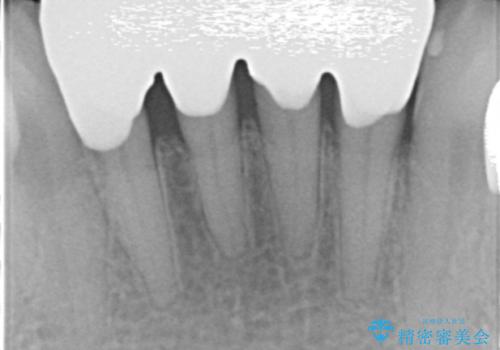

前歯がかけた、ぐらぐらする 60代女性

- 下の前歯が欠けてぐらぐらすることを主訴に来院された患者様です。

以前行った奥歯の治療により下顎前歯の動揺は改善傾向にあり顕著ではなかったのですが、欠けて黒くなっていることと少しの動揺が気になるとのことでした。

元気なうちに治療しておきたいという患者様の強いご希望により、下顎前歯の連結補綴と欠けている小臼歯の補綴治療を行いました。

クラウンを連結することにより気にされていた動揺もなくなり、安心して頂けました。

被せ物の種類:オールセラミッククラウン スタンダード